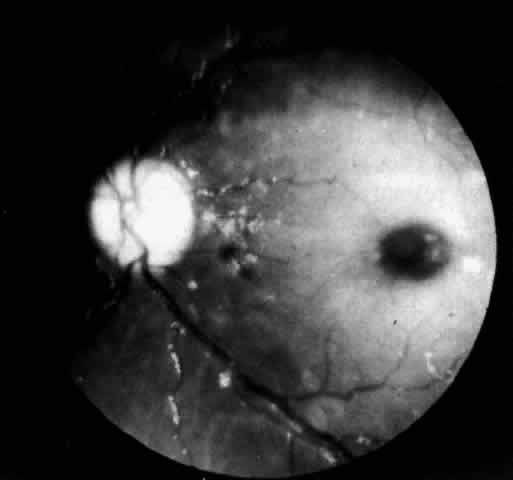

by Farher in 1949; by 1952 he had observed two additional cases.91 There are now more than 28 reported cases in the literature.92,93 CLINICAL MANIFESTATIONS. The disease begins in the first few weeks of life and presents as irritability, vomiting, hoarseness, failure to thrive, and painful swollen joints. Subcutaneous periarticular nodules develop, especially at the ankle and elbow joints. Hoarseness is severe because of progressive granulomatous infiltration of the epiglottis and larynx. Disturbance in swallowing with episodic bouts of fever and pulmonary consolidation is common. Some infants develop systolic murmurs owing to valvular involvement. Most have a generalized lymphadenopathy with occasionally moderate hepatomegaly and rarely splenomegaly. Characteristically intellect is unaffected and involvement of the nervous system is not a prominent feature.91 However, hypotonia and diminished deep tendon reflexes due to a peripheral neuropathy and anterior horn cell involvement have been reported. In such cases electromyographic studies show signs of denervation and elevated cerebrospinal fluid protein. Most children do not survive the fourth year, although a few cases of intermediate severity with longer survival have been reported.94 OCULAR MANIFESTATIONS. The retinal changes in Farber's disease are subtle and easily overlooked. The fundi of one 8-month-old patient had been examined several times following the onset of the disease at age 2 weeks and considered to be normal. Cogan and colleagues95 subsequently observed and reported a diffuse grayish opacification of the retina about the fovea, producing a mild cherry-red spot (Fig. 9). The parafoveal opacity differed from that seen in Tay-Sachs disease in that the opacity was pale gray instead of white and it was accompanied by little, if any, pallor of the optic disc. Shortly before death at age 11 months there was a suggestion of a peppery pigmentation of the entire retina and some abnormal pigmentation in the macula. The retinal vessels showed no abnormality. Visual function, as judged by the patient's attentiveness, retention of the optokinetic response, and absence of nystagmus, was normal. Zetterstrom's patient with Farber's disease had no retinopathy.96 At age 17 months he developed a xanthoma-like growth approximately the size of a rice grain in the conjunctiva over the left eye. Microscopic examination of the excised conjunctival granuloma showed a similar histologic picture to that of a subcutaneous granuloma, with groups of irregularly formed large foam cells with granular cytoplasm weakly positive in reaction to fat stains. François97 has reported central macroscopic subepithelial corneal opacities in two children with Farber's disease. NEUROPATHOLOGY. The characteristic pathologic lesion in Farber's disease is a granuloma containing foam cells filled with PAS positive material extractable with lipid solvents. Ultrastructural examination of these cells has shown cytoplasmic vacuoles limited by a single membrane and containing comma-shaped tubular structures. The vacuoles are acid phosphatase positive and probably represent lysosomes. They are called Farber bodies. Elevated levels of ceramide have been found in subcutaneous nodules in the liver, kidney, brain, and lungs. In the brain, neurons and glial cells are distended owing to the accumulation of ceramide and gangliosides. Routine sections of the paraffin-embedded eye tissue show no histologic abnormalities in Farber's disease, but frozen, unstained sections show birefringent lipid crystals in the ganglion cells of the retina. The accumulation of lipid is most conspicuous in the parafoveal region of the macula where the ganglion cells are abundant. In spite of their distention, the engorged cells remain intact and there are no extracellular deposits of lipid in the retina. The optic nerve is not atrophic.95Cogan and colleagues95 performed solubility studies in several of the organic solvents and determined that the intracellular deposit in the ganglion cells was likely to be a complex lipid rather than neutral fat or cholesterol. DIAGNOSTIC TESTS. The isolation of excess ceramide in biopsied tissue is no longer required to confirm the diagnosis of Farber's disease.98 Determination of ceramidase levels in leukocytes and cultured fibroblasts is the diagnostic procedure. The assay shows low to absent enzyme activity. Carriers are identified by demonstration of half normal levels of enzyme activity in cultured fibroblasts. Prenatal diagnosis has been accomplished in four pregnancies at risk by assaying cultured amniocytes .99 |